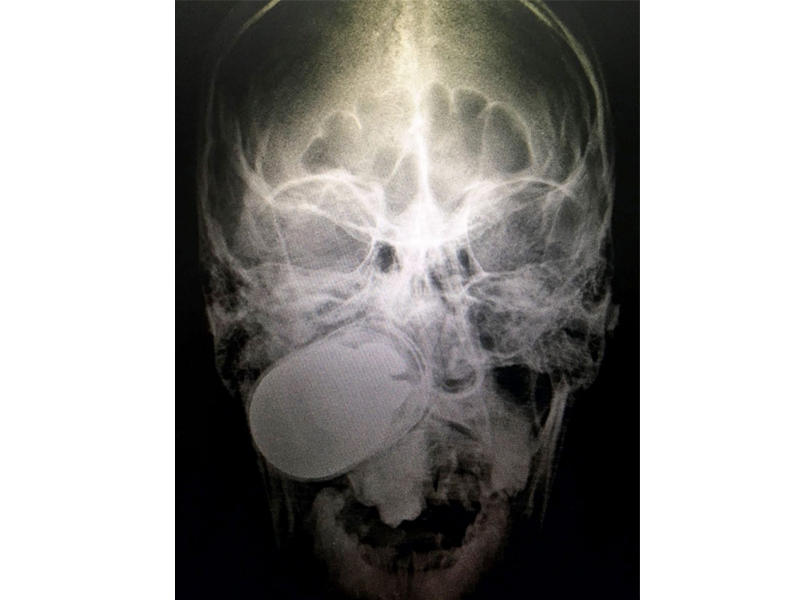

أزال أطباء في الجيش الكولومبي قنبلة حية من رأس جندي. وكان جندي قد أطلق قنبلة خطأً من قاذفة قنابل أثناء دورية في أروكا بالجزء الشرقي من البلاد، فاستقرت القنبلة في رأس زميله. وذكرت صحيفة "إل تييمبو" أن نقل الضحية بطائرة...